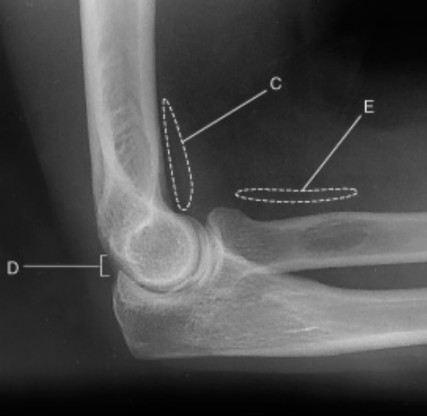

On this true lateral elbow projection, what does C represent?

anterior fat pad

On this true lateral elbow projection, what does the teardrop shape represent?

On this true lateral elbow, describe the appearance of C

anterior fat pad is teardrop shape

On this true lateral elbow projection, what does D represent?

posterior fat pad

On this true lateral elbow projection, when does the posterior fat pad become visible?

only visible when there is pathology

On this true lateral elbow projection, what does E represent?

supinator fat stripe

On this true lateral elbow projection, which fat pad is only demonstrated when there is pathology?

On this true lateral elbow projection, when is E commonly used for? Hint: used to d______

may be used to diagnose radial head or neck fractures